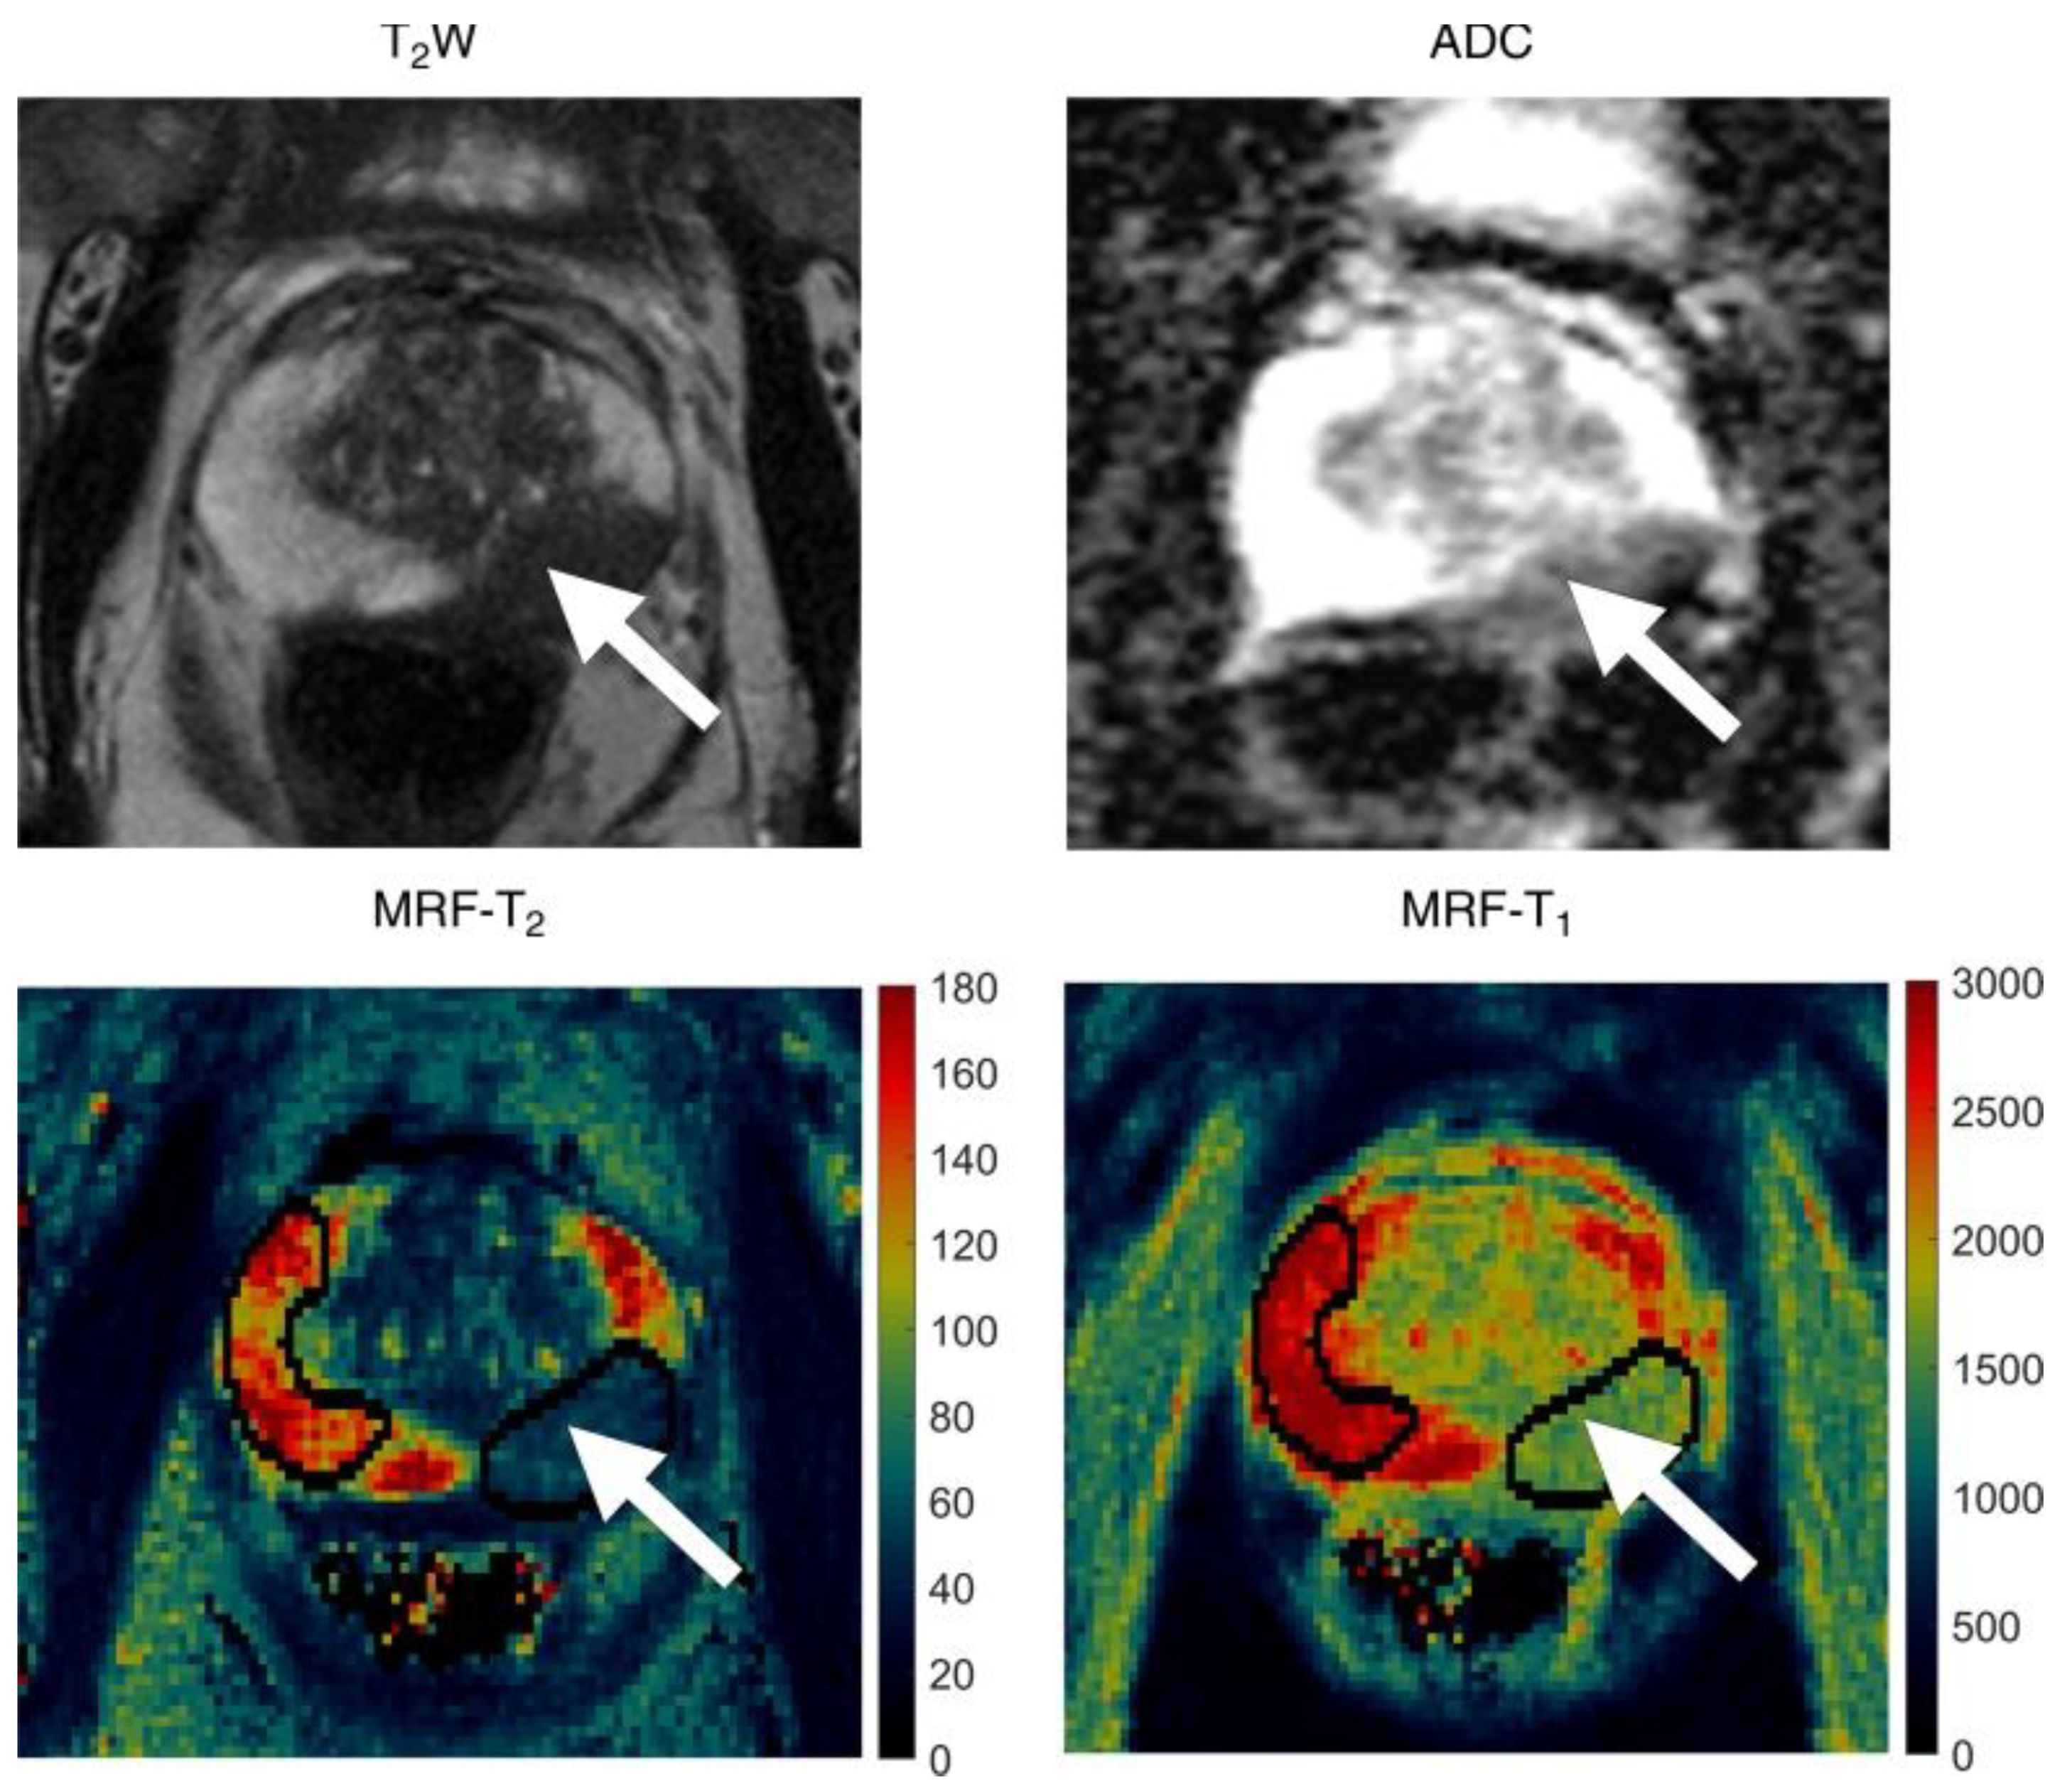

An initial retrospective study from Yu et al. [62] showed that a 3.0-T unit MRF combined with standard ADC mapping had high sensitivity for differentiation between peripheral zone prostate cancer and normal prostate tissue (Figure 4). The acquisition time of MRF was also shorter than the acquisition time for standard clinical sequences used in that institution when acquiring T1, T2, and ADC maps (average of 7.5 min versus 21 min). T1, T2 signal intensities and ADC values reported were all lower in cancers compared with normal peripheral zones in the prostate, with reported mean cancer T1 of 1628 ms (±344) and mean T2 of 73 ms (±27), in contrast to 2247 ms (±450) and 169 ms (±61), respectively, for a normal gland. The T1 value changes detected with MRF had not been previously reported, possibly due to difficulties in measuring T1 signal intensity changes on conventional weighted MRI images. These findings were also in agreement with the study results from Panda et al. in which biopsy was used as the reference standard [63]. Panda et al. also reported that T2 and ADC values together could separate clinically significant cancer from low-grade cancer in the peripheral zone. Another retrospective study by Panda et al. showed that T1/T2 MRF combined with a separately acquired ADC mapping may improve lesion characterization in the transition zone of the prostate [64]. MRF T1 and ADC values were found to be complementary for malignant lesion staging, whereas there was an overlap in MRF T2 values between different lesion types [64]. Han et al. recently used 3D MRF in phantoms and 90 patients with suspected prostate cancer [65]. Findings were consistent with the results from 2D MRF trials for prostate cancer, and the image acquisition protocol provided faster coverage of the entire prostate gland (4 min rather than 7–8 min). Considering that the studies cited above were from individual institutions, multi-institutional datasets with bigger sample sizes will improve the generalisability and repeatability of the findings. However, the consistent results obtained from separate independent preliminary trials are encouraging. High inter-scanner reproducibility of MRF T1 relaxometry was reported for assessing healthy prostate recently for both 1.5T and 3T MRI scanners [66]. Similar studies in patients with suspected prostate cancer have yet to report their findings. To date, MRF has been used for the characterization of prostate lesions but not detection as a higher resolution is required for structural T2-weighted imaging. This modality may also benefit from the development of simultaneous MRF mapping of T1, T2, and ADC to eliminate the risk of misalignment. Jiang et al. inserted multiple magnetization preparation modules in a FISP-based MRF sequence to achieve simultaneous T1, T2, and ADC mapping in less than 60 s per slice [67]. Prostate imaging may benefit from further developments of this novel MRF sequence. The feasibility of guiding RT or monitoring treatment response for prostate cancer using MRF has also yet to be investigated.

Figure 4.

Images in 72-year-old man referred for an elevated prostate-specific antigen of 9.87 ng/mL with minimal urinary symptoms. Patient underwent limited MR imaging and targeted biopsy of lesion in left mid prostate. Prostate adenocarcinoma with Gleason score 4 + 3 = 7 was diagnosed at cognitively targeted biopsy. T2-weighted image (T2W), ADC apparent diffusion coefficient map, MR fingerprinting (MRF)—T2 map, and MR fingerprinting—T1 map show corresponding hypointense lesion in left mid prostate (arrow) and NPZ normal-appearing peripheral zone in right hemi-prostate. Reprinted with permission from ref. [62]. Copyright 2020 The Radiological Society of North America (RSNA).